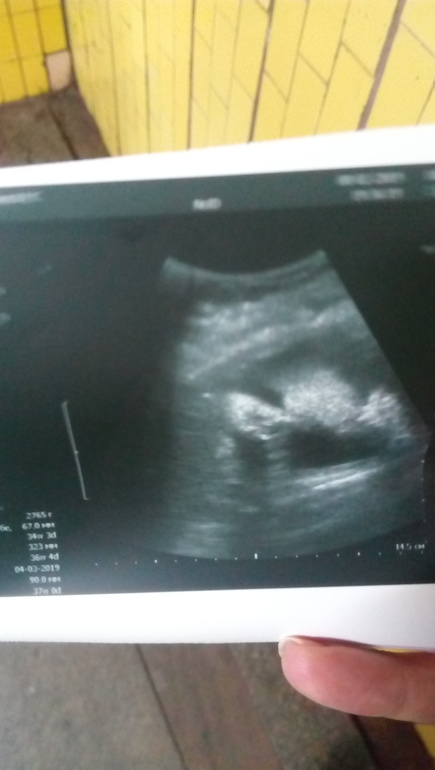

И так сегодня по М ровно 35 недель, а вот по УЗИ что я делала вчера уже 36+1.😱

Конечно я немного охренела. Когда врач перенес пдр на 8 марта. Как? Мужик и на 8 марта. Голова и живот вообще на 37 недель. Ну и вес наш 2800😱 Я конечно понимала что будет не маленький, девки то у меня тоже не дюймовочки, но не до такой же степени. Из плохого плацента 3 степени, врач ничего не сказал, в пн пойду к своему Г, уж очень меня это пугает.

Ну и по традиции снимок моего сыночка)

Надеюсь хоть кто-то поймет что на фото, а то из моих никто ничего не понял кроме меня 😂